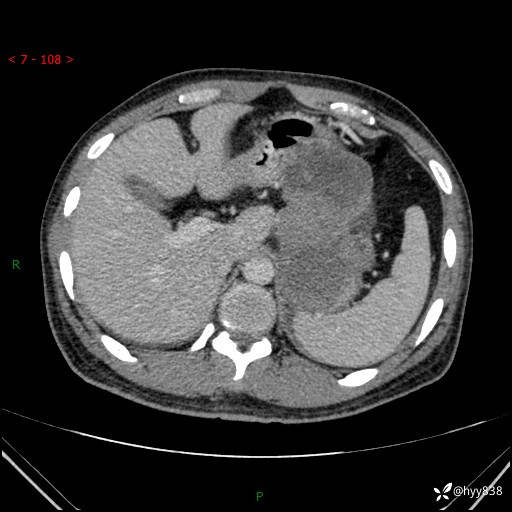

病例39岁/女,左侧腰痛入院。腹腔囊实性肿块,定位、定性---结果公布~

性别:男

年龄:39岁

简要病史:左侧腰痛待查,CT发现腹腔占位

腹部CT平扫+增强